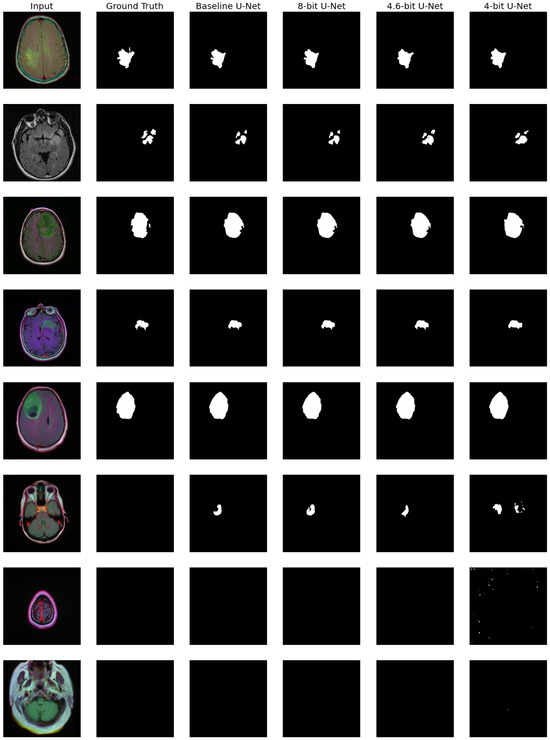

Let us now consider the U-Net model [45]. It inputs RGB MRI images and predicts abnormality regions as binary masks. Some examples of such inputs and outputs are presented in Figure 6.

Figure 6.

Results of quantized U-Net evaluation on TCIA images.

We also computed several metrics to evaluate the resulting quality. We used Dice and Intersection over Union (IoU) scores to calculate segmentation accuracy (averaged over images at which abnormality exists). We also considered binary classification metrics (is there abnormality or not): accuracy, precision, recall, type I errors (false positive), and type II errors (false negatives). All those metrics are presented in Table 8.

From Figure 6 and Table 8, we can see that eight-bit quantization is slightly better than the baseline: it increases type I error but, to some degree, improves the segmentation results. However, four-bit quantization leads to severe quality degradation and noticeable noise-like artifacts in Figure 6. At the same time, 4.6-bit quantization preserves reasonable quality, comparable to eight-bit and baseline.